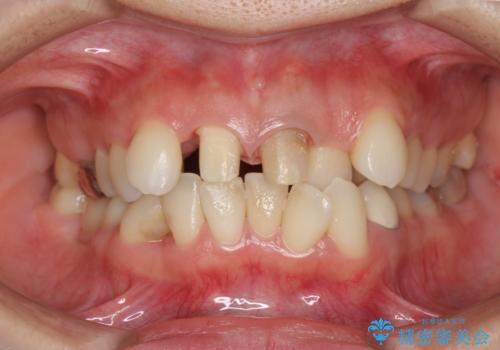

著しいがたつきによる清掃困難 歯牙抜去とセラミック治療

- 前歯の変色の改善を希望され来院されました。

X線写真より、充填剤の突き出た状態の根管治療の再治療を行い、セラミック治療を計画すると同時に、

歯ブラシがしづらく虫歯の原因となっている歯の位置の悪い右上側切歯の抜去を行います。

清掃を難しくしている歯を抜去することで虫歯の再発を防ぐような治療方針としました。